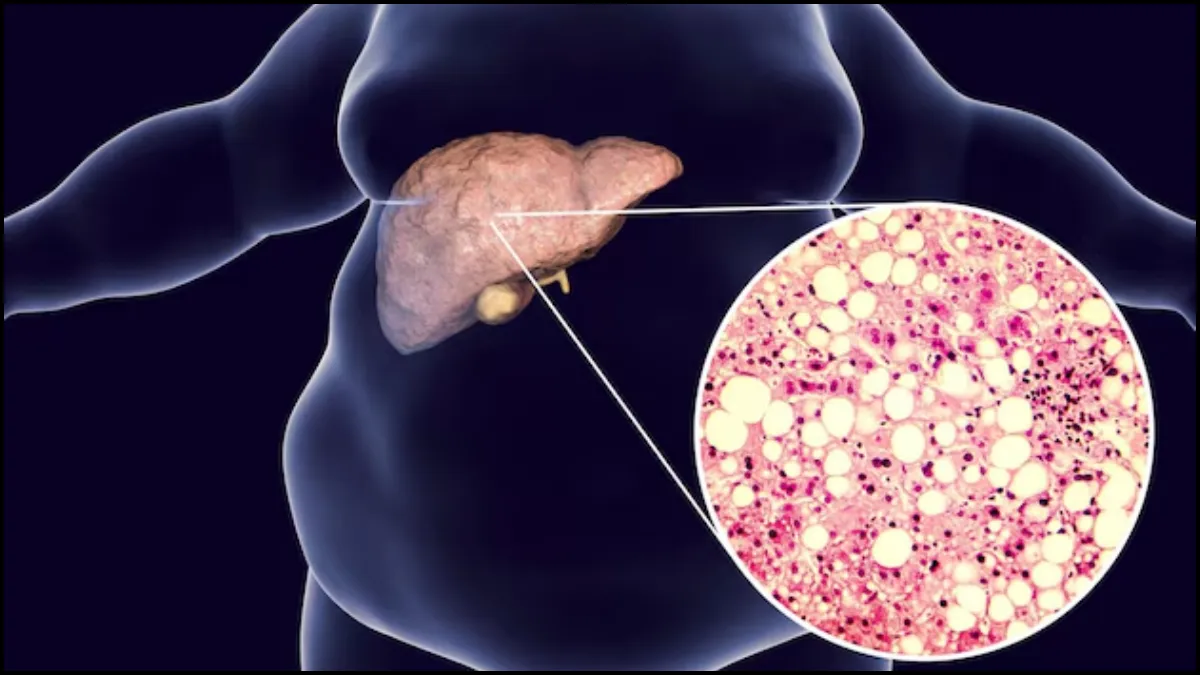

भारत में फैटी लिवर (Fatty Liver) के मरीजों की संख्या लगातार बढ़ रही है। विशेषज्ञों के अनुसार, हर तीसरा भारतीय इस बीमारी से प्रभावित है। फैटी लिवर न केवल लिवर की कार्यक्षमता को नुकसान पहुंचाता है, बल्कि डायबिटीज, हृदय रोग और अन्य गंभीर जटिलताओं का भी कारण बन सकता है। अब तक फैटी लिवर के लिए कोई प्रभावी दवा मौजूद नहीं थी, और मरीज केवल जीवनशैली सुधार, व्यायाम और खान-पान पर निर्भर रहते थे।

प्रोफेसर अशोक कुमार के अनुसार, यह स्प्रे स्वस्थ कोशिकाओं से प्राप्त एक्सोजोम्स (Exosomes) को विशेष पॉलिमर सॉल्यूशन में मिलाकर तैयार किया जाता है। लेप्रोस्कोपिक (minimally invasive) तकनीक के जरिए लिवर में स्प्रे किया जाता है। शरीर में पहुंचते ही यह तरल जैल में बदल जाता है और क्षतिग्रस्त लिवर कोशिकाओं को रिपेयर करता है। इसके साथ ही फैट जमा होने की प्रक्रिया रुकती है और लिवर नए जैसा स्वस्थ बनने लगता है।

प्रारंभिक परीक्षण चूहों पर किए गए हैं, जहां स्प्रे के इस्तेमाल से फैटी लिवर पूरी तरह सामान्य हो गया। टीम ने दावा किया कि स्प्रे का असर एक हफ्ते में दिखना शुरू हो जाता है और 2-3 महीनों में लिवर पूरी तरह रिकवर हो सकता है।